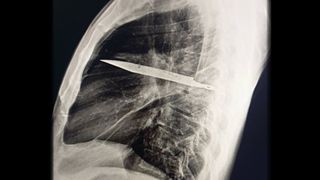

A knife broke off in a man's chest, and he didn't notice it for 8 years

Diagnostic dilemma A man noticed pus oozing from his chest, and it ended up revealing a knife blade in his thoracic cavity.